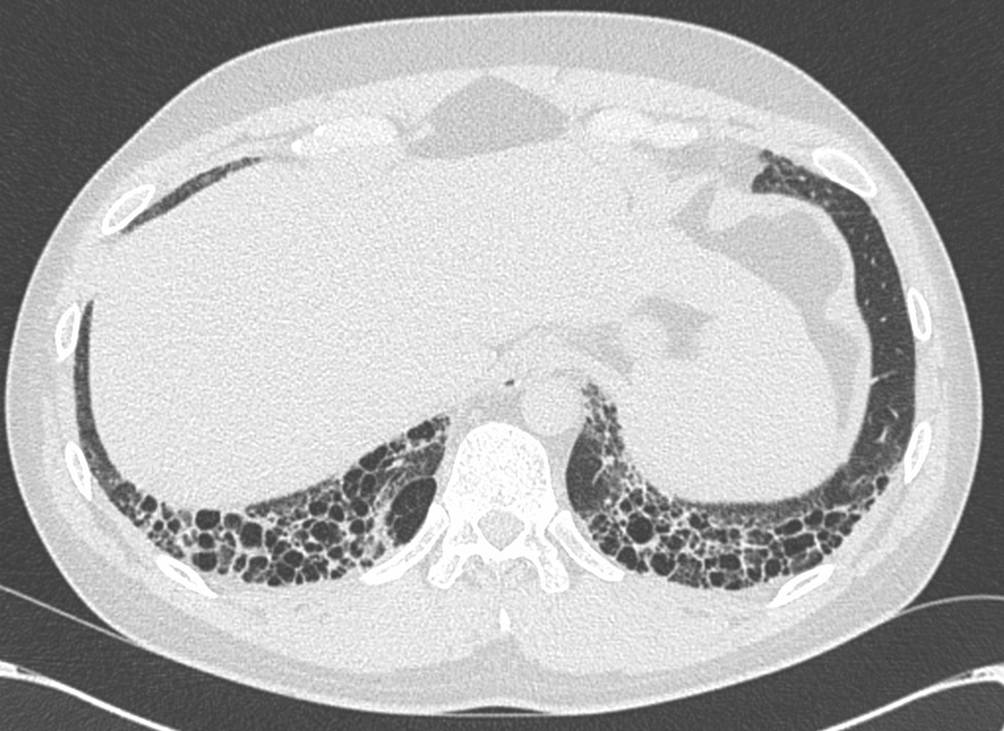

Die Computertomographie ist der Lungenfunktion in der Frühdiagnose einer ILD überlegen [35]. In der CT manifestiert sich die SSc-ILD meist (80 %) unter dem Bild einer nicht-spezifischen interstitiellen Pneumonie (NSIP). Die typischen Veränderungen sind dabei Milchglasverdichtungen neben einer variablen Ausprägung von retikulären Veränderungen in einer basalen und peripheren Verteilung mit häufiger subpleuraler Aussparung (Abb. 1).

Abb. 1

CT einer 27 Jahre alten Patientin mit einer bekannten Sklerodermie. Es finden sich in der Peripherie beider Unterlappen Milchglasverdichtungen und retikuläre Verdichtungen, vereinbar mit einer nicht-spezifischen interstitiellen Pneumonie (NSIP)